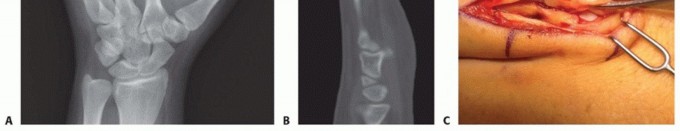

Standard radiographic imaging forms the cornerstone of diagnostic evaluation, requiring, at minimum, a dedicated posteroanterior (PA), a true lateral, and a pronated oblique view of the injured hand. The PA view is excellent for assessing coronal plane angulation and transverse displacement, though it notoriously underestimates sagittal plane deformity. The true lateral view is critical for quantifying apex-dorsal angulation, though overlapping metacarpal shadows can complicate interpretation. The pronated oblique view often provides the clearest visualization of the fracture profile and the degree of comminution.

When standard radiographs are equivocal, or when dealing with complex intra-articular fractures and suspected CMC fracture-dislocations, advanced cross-sectional imaging is mandatory. High-resolution Computed Tomography (CT) with 3D reconstructions provides unparalleled detail of articular step-offs, occult comminution, and the precise spatial orientation of fracture fragments. This information is invaluable for determining the feasibility of lag screw fixation versus the necessity of bridge plating. Furthermore, obtaining radiographs of the uninjured, contralateral hand serves as a vital anatomical template, allowing the surgeon to accurately gauge the patient's native metacarpal length and intrinsic diaphyseal curvature.

Clinical & Radiographic Imaging Archive